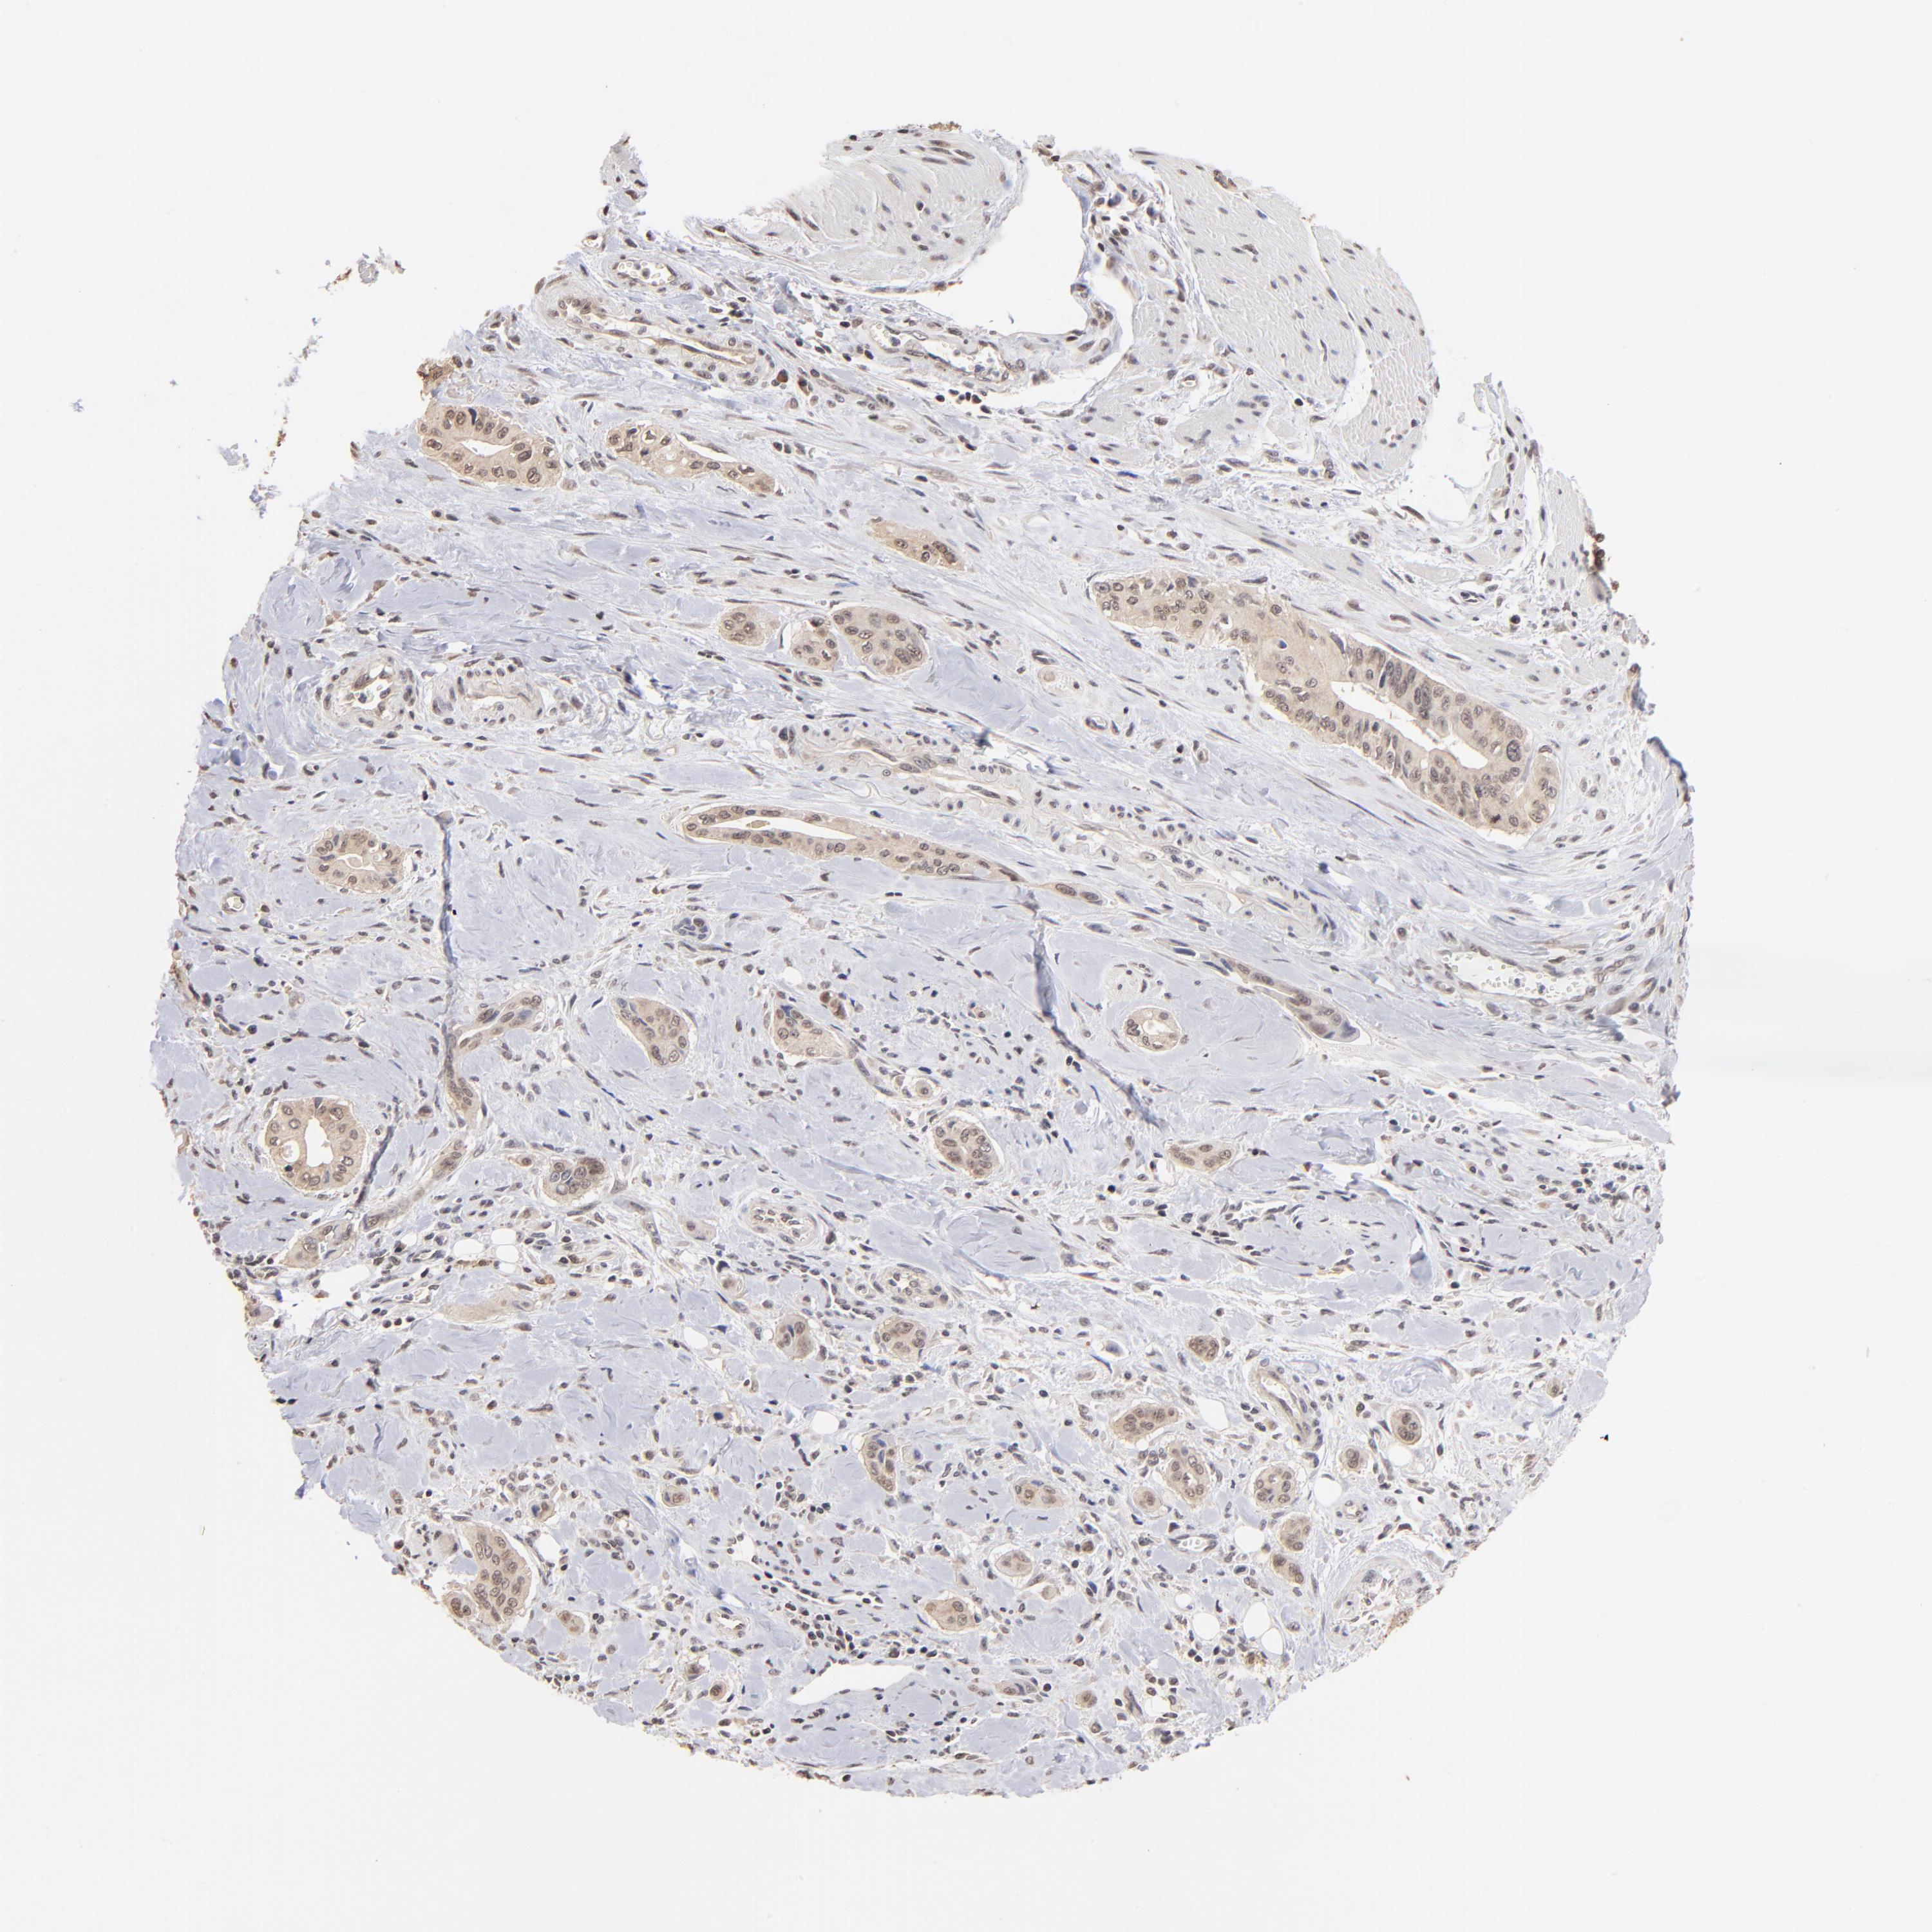

PANCREATIC CANCER - Protein expressioni

A mouse-over function shows sample information and annotation data. Click on an image to view it in a full screen mode. Samples can be filtered based on level of antibody staining by selecting one or several of the following categories: high, medium, low and not detected. The assay and annotation is described here.

Note that samples used for immunohistochemistry by the Human Protein Atlas do not correspond to samples in the TCGA dataset.

Antibody stainingi

Antibody staining in the annotated cell types in the current human tissue is reported as not detected, low, medium, or high, based on conventional immunohistochemistry profiling in selected tissues. This score is based on the combination of the staining intensity and fraction of stained cells.

Each image is clickable and will lead to virtual microscopy that enables deeper exploration of all samples and also displays staining intensity scores, fraction scores and subcellular localization as well as patient and tissue information for each sample.

Antibody HPA003359

Staining

High

Medium

Low

Not detected

Intensity

Strong

Moderate

Weak

Negative

Quantity

>75%

75%-25%

<25%

None

Location

Nuclear

Cytoplasmic/membranous

Cytoplasmic/membranous,nuclear

Adenocarcinoma, NOS

Adenocarcinoma, metastatic, NOS